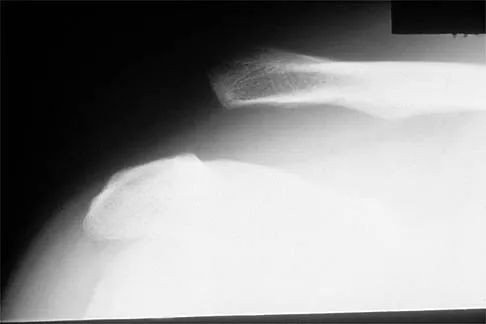

What muscle attaches to the site shown by the arrow in Figure 2?

Explanation

The latissimus dorsi inserts on the humerus metaphysis between the pectoralis major (posterior) and teres major (anterior). Teres minor inserts on the base of the greater tuberosity. Pectoralis minor does not insert on the humerus. Williams PL, Warwick R, Dyson M, Bannister LH: Neurology, in Gray's Anatomy, ed 37. Edinburgh, Scotland, Churchill Livingstone, 1989, pp 1131-1132.